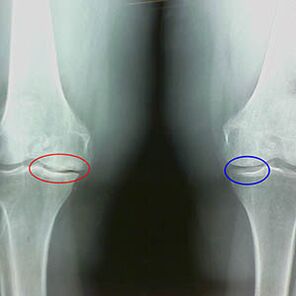

Ο προσδιορισμός του βαθμού αρθρίσεως συμβαίνει με x -rayΑποκαλύπτοντας τη συμμετοχή στην παθολογική διαδικασία των οστών. Η αλλαγή τους δείχνει ότι το μυϊκό σύστημα βρίσκεται σε ανισορροπία για 5-10 χρόνια. Κατά κανόνα, άνθρωποι Για αρκετά χρόνια βιώνουν πονηρά πόνους.

Στο πρώτο στάδιο της αρθρίσεως, η οποία ανιχνεύεται τυχαία, εμφανίζεται μια μικρή αύξηση των οστών των οστών. Οι αυξήσεις εμφανίζονται σε μέρη της μεγαλύτερης αστάθειας της άρθρωσης. Συνήθως, οι ασθενείς σπάνια αντιμετωπίζουν πόνο ή δυσφορία κατά τη διάρκεια της κίνησης.

Το δεύτερο στάδιο της αρθρίσεως θεωρείται εύκολο. Η ακτινογραφία αποκαλύπτει σημαντικά οστά οστά, αλλά ο χόνδρος δεν επηρεάζεται. Η ποσότητα του αρθρικού υγρού μειώνεται, αλλά τα συμπτώματα του πόνου εμφανίζονται μετά από μακρύ περπάτημα και τρέξιμο, δυσκαμψία στην άρθρωση και πόνο όταν κάμπτονται και στη θέση στα γόνατα.

Πρώιμα χαρακτηριστικά X -Ray του δεύτερου σταδίου της αρθρίδας του γόνατος:

- Οι αιχμηρές άκρες των διαστολέων μεταξύ της κνήμης, όπου συνδέεται ο σταυροειδής σύνδεσμος.

- στενότητα του χάσματος των αρθρώσεων στη μέση πλευρά.

- Οι αιχμηρές άκρες των κονδύλων των οστών στις μέσες πλευρές, λιγότερο συχνά σε πλευρική - ανάλογα με την ανάπτυξη της παραμόρφωσης του Valgus ή της Varior.

Για το δεύτερο στάδιο στο Larsen Η στένωση του κοινού χάσματος κατά περισσότερο από 50% είναι χαρακτηριστική είναι χαρακτηριστική, αλλά αυτό μπορεί να ελεγχθεί μόνο σε δυναμική ή σύγκριση με μια αντίθετη άρθρωση.

Η ακτινογραφία δείχνει την παρουσία οστεοφυτών, μια αλλαγή στο διάστημα μεταξύ των οστών του μηριαίου και της κνήμης, γεγονός που υποδεικνύει την απώλεια του χόνδρου στο γόνατο. Μερικές φορές η x -ακινητοποίηση των αρθρώσεων του γόνατος δείχνει σημαντικά σημάδια φθοράς χόνδρου, αλλά οι ασθενείς δεν παρουσιάζουν σημαντικό πόνο.Αντίθετα, η αρθρέωση του πρώτου σταδίου μπορεί να διαταράξει τη λειτουργία του γόνατος, δεδομένου ότι η αιτία του πόνου είναι υποτονικοί μύες.